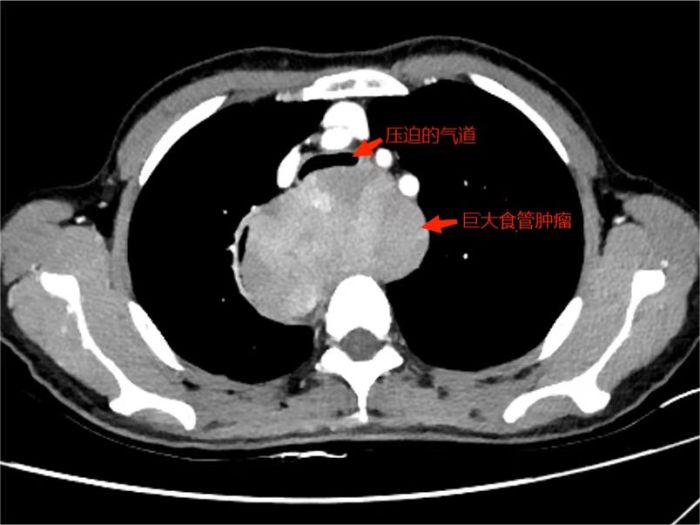

熊荣生主任在仔细研究金阿姨的病情和检查结果后,考虑到食管大肿瘤(10.2cm×8.2cm×5.8cm)压迫气道引起气道狭窄。若继续保守治疗,随着肿瘤的继续增大,呼吸及吞咽困难的症状将会持续加重。若考虑进行手术切除,可能出现麻醉时通气困难、麻醉后气管软化塌陷,造成窒息缺氧危及生命。

影像图